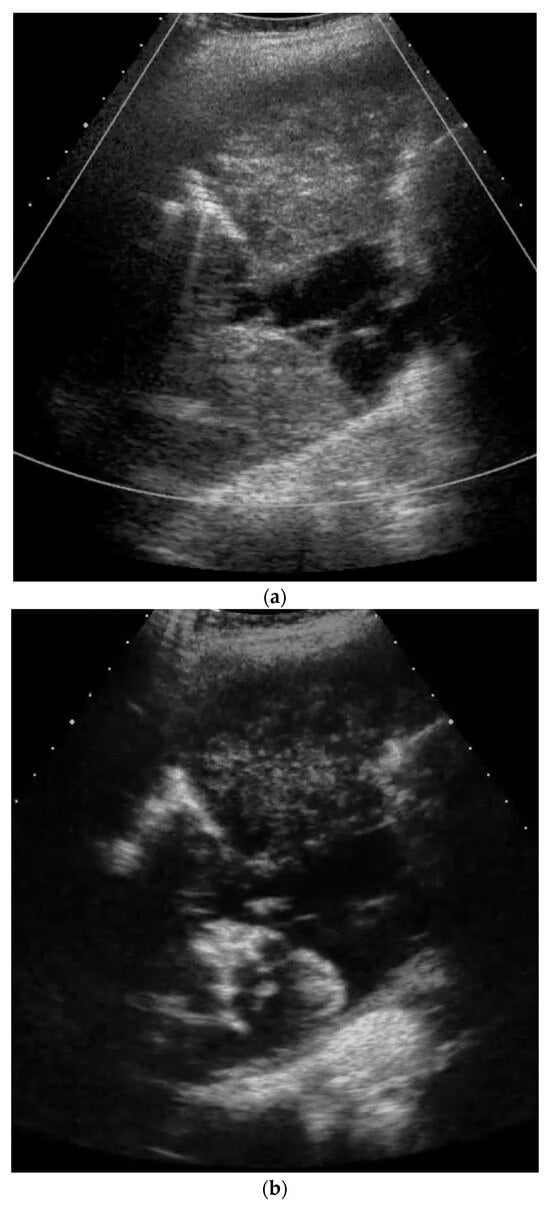

2. Primary Pulmonary Sarcomas